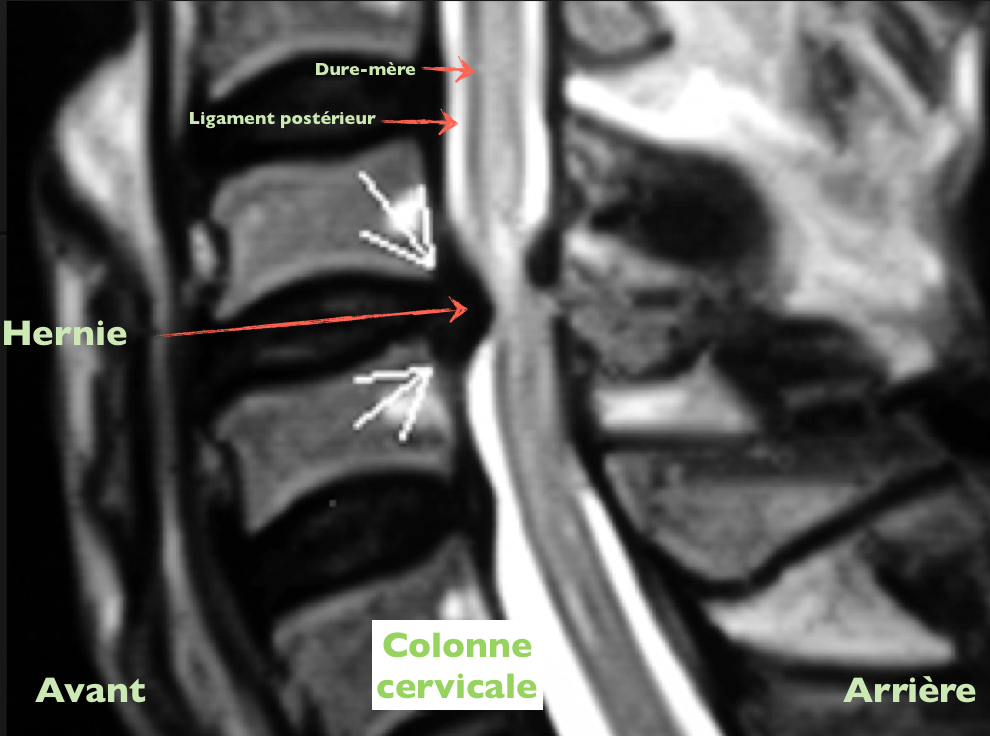

Disque. Ligament post. Dure-mère Publié 4 octobre 2013 à 990 × 736 dans Les disques et vos douleurs ← Précédent Suivant → J’aime chargement… Poster un commentaire ou un rétrolien.